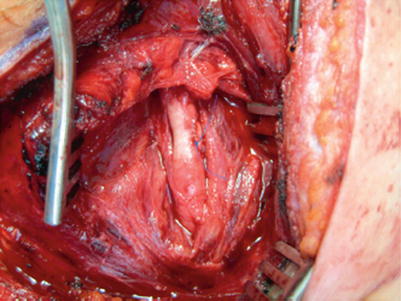

Fig. 29.3

Gunshot wound to the common carotid injury repaired with a bovine pericardial patch

Stab wounds are more likely repaired primarily given the lack of associated tissue loss or blast effect. All GSW need to be debrided prior to repair and are unlikely to allow primary repair (as seen in Fig. 29.3) without tension. Patch repair can be performed with a synthetic patch or a biologic patch (e.g., bovine pericardium, saphenous vein graft). The biologic or synthetic patches may be quicker than saphenous vein graft with no major downside. Interposition synthetic grafts (PTFE or Dacron 6 mm) are also easy to use and have excellent patency rates.